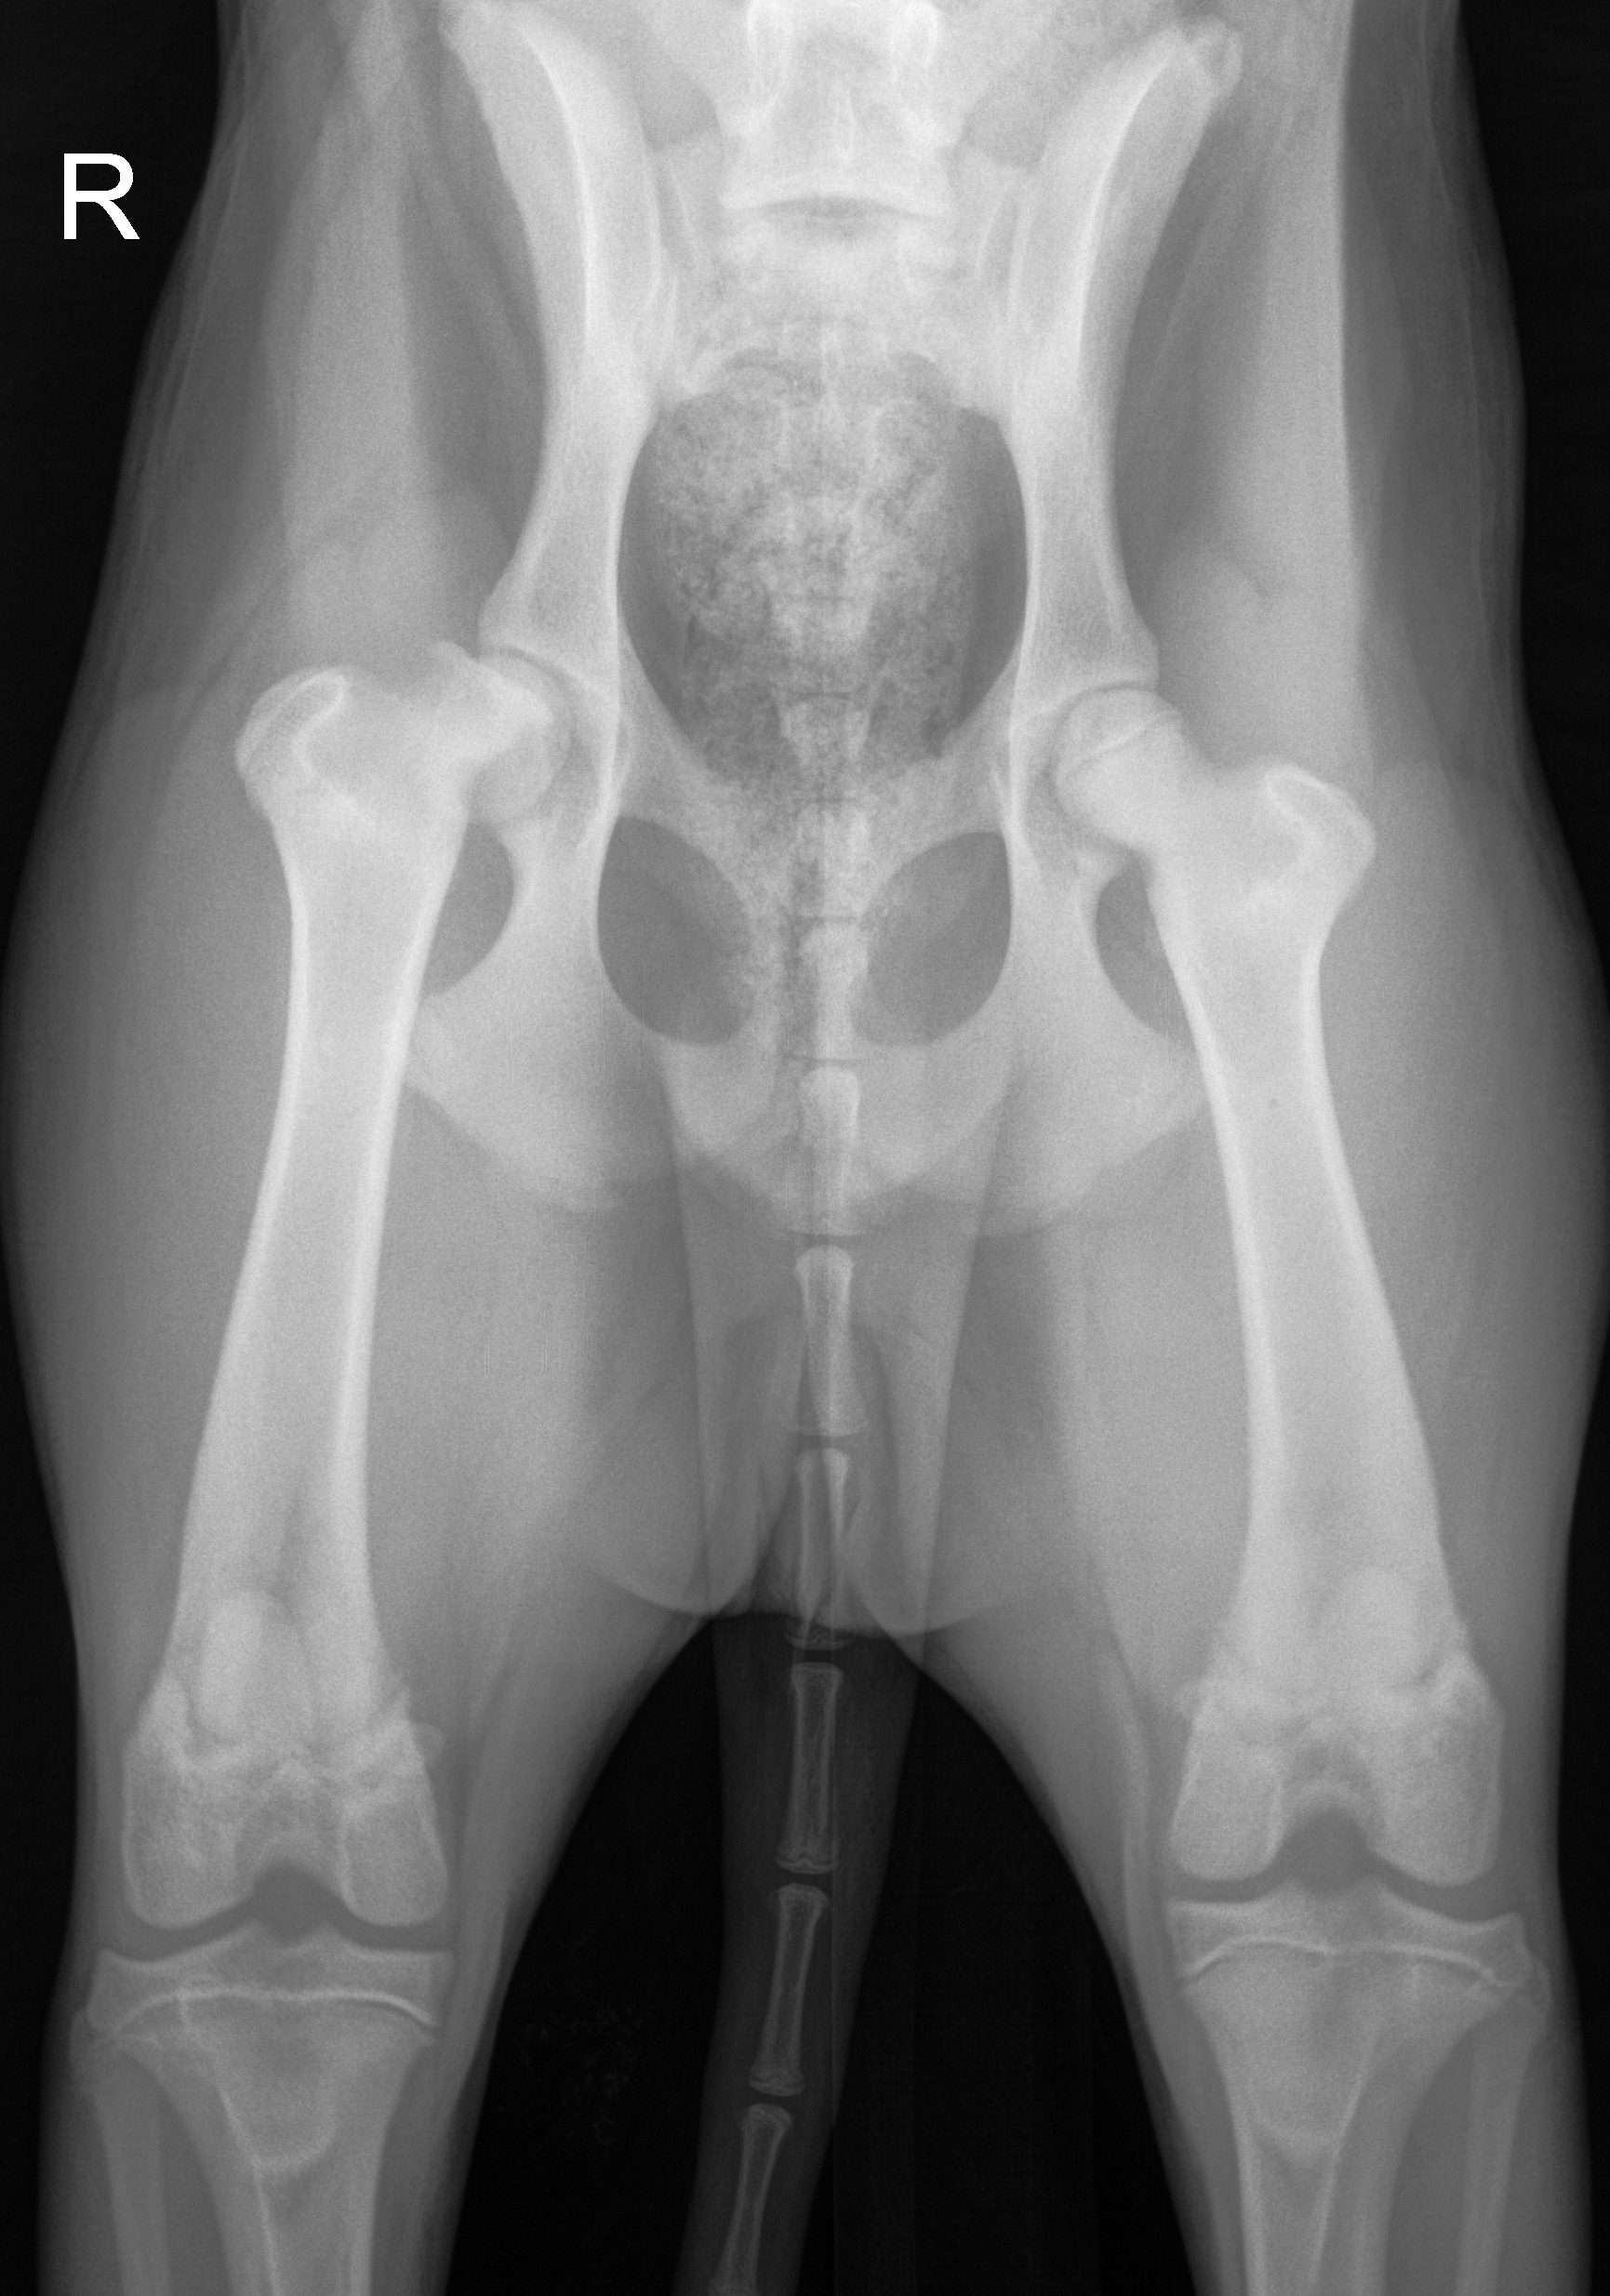

We carefully got her into a customers vehicle and brought her up to the range. After bathing her and waiting to see if anyone would come forward, we took her to the veterinarian last night. After $600 in exams and X-rays, we learned the heartbreaking news — she has a broken hip.

The veterinarian believes she may have been hit by a car or injured by cattle. She is still trying to walk and even puts some weight on the leg, but the injury is severe and she will need orthopedic surgery to repair the hip and live a normal life.

Without surgery she could live in chronic pain or lose proper use of the leg.